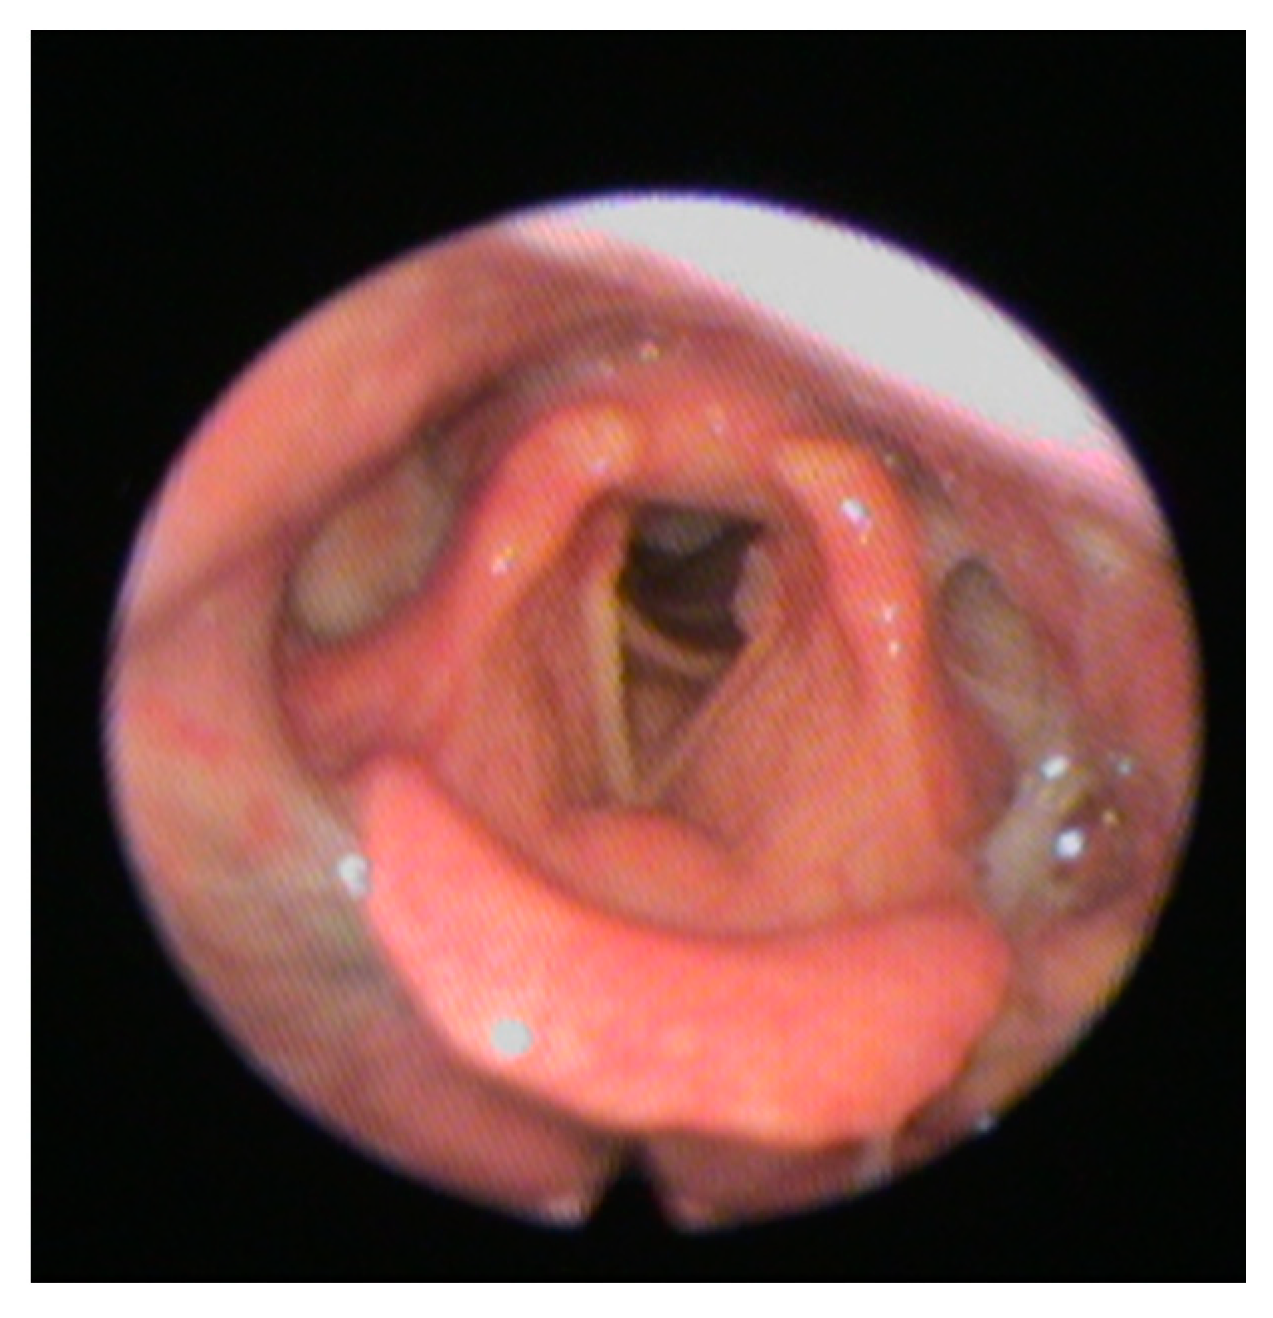

The FEES is a transnasal passage of a flexible nasopharyngoscope to provide direct observation of the pharynx and larynx before and after the swallow [51]. This latter is preferable in cooperative patients with suspect silent aspiration and is practical especially in cases where there is uncertain inhalation or contributing factors, such as a risk of cough ineffectiveness. FEES allows a good view of stagnation in the valleculae, in the pyriform sinuses, in the laryngeal vestibule (Figure 2).

Figure 2.

Shows a typical fiberoptic endoscopic evaluation of swallowing (FEES) image.

Furthermore, stimulation with the tip of the endoscope permits to trigger the pharyngeal and laryngeal zones.